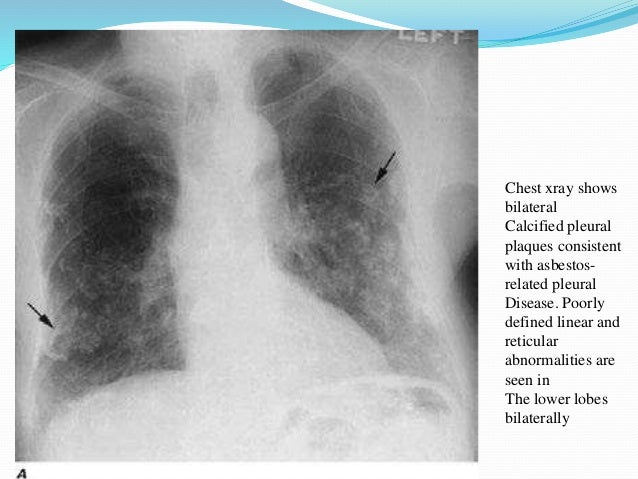

Lung disease asbestos. Some conditions for example mesothelioma or lung cancer are more serious than others. Asbestos related diseases include non malignant disorders such as asbestosis pulmonary fibrosis due to asbestos diffuse pleural thickening pleural plaques pleural effusion rounded atelectasis and malignancies such as lung cancer and malignant mesothelioma. All forms of asbestos increase the risk of lung disease.

The three types of asbestos related lung disease are scarring asbestosis non cancerous disease of the tissue of the lining of the surface of the lung pleural disease and lung cancer of the lungs or their outer lining tissue mesothelioma. Asbestosis is a progressive disease meaning scarring continues and symptoms worsen with time. Complications may include lung cancer mesothelioma and pulmonary heart disease.

Asbestos is a mineral that is found naturally in rocks and soil. Generally it requires a relatively large exposure over a long period of time. Asbestos related diseases are disorders of the lung and pleura caused by the inhalation of asbestos fibres.